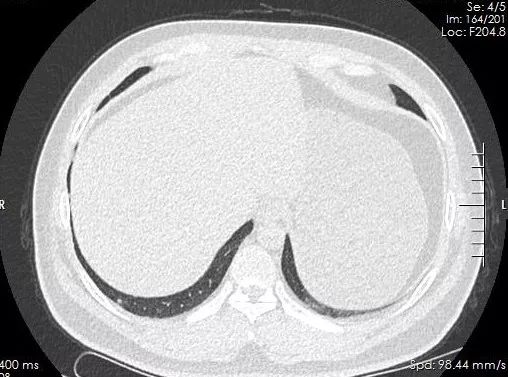

常规CT辐射剂量较大,这台先锋能谱CT可降低80%以上的辐射剂量,满足绿色低剂量扫描要求。通过此项技术,可安全开展更加权威的低剂量肺癌筛查,以满足广大患者的体检需求。

王先生想通过胸部CT筛查肺癌,由于担心辐射问题迟迟未下决定,听说新区中医医院放射科引进了一台能谱CT可以做低剂量扫描,他马上挂号并完成了检查。现在,再也不用担心体检时害怕吃射线的问题啦!